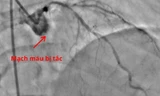

Sau khi tình trạng tuần hoàn được kiểm soát, bệnh nhân được chuyển an toàn đến phòng can thiệp tim mạch. Kết quả chụp mạch cho thấy một nhánh động mạch vành nuôi tim bị tắc hoàn toàn. Các bác sĩ đã nhanh chóng can thiệp tái thông mạch máu và đặt stent, giúp khôi phục dòng máu nuôi tim.